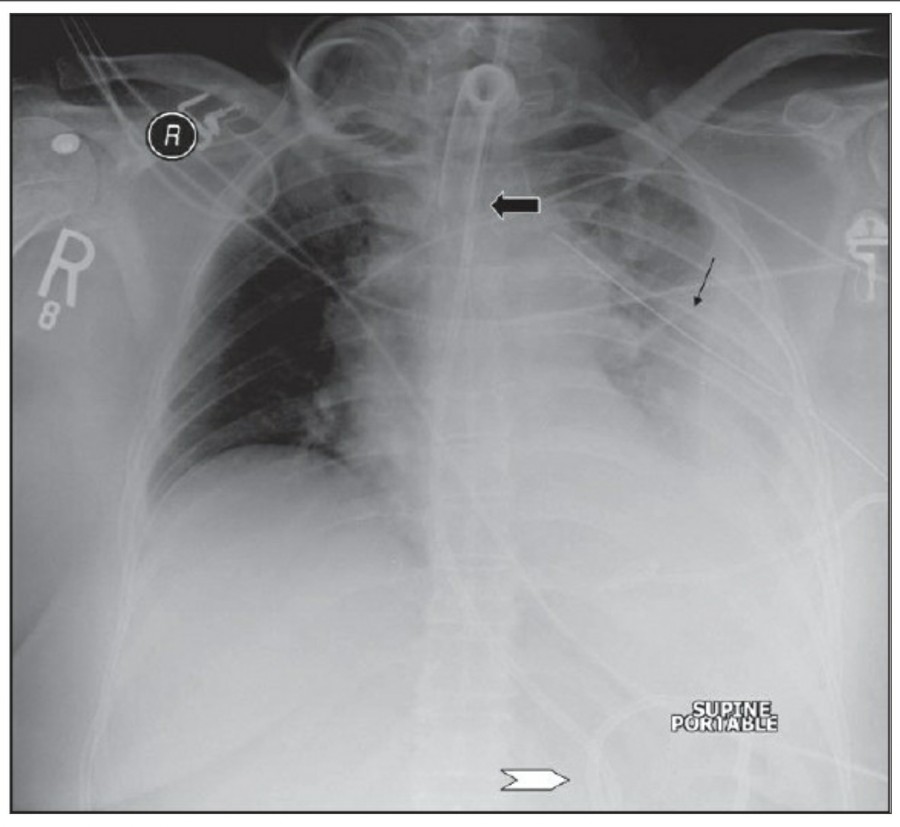

첫 poratable chest X ray 촬영은 각종 line과 device의 위치를 확인하는 데 꼭 필요하며, 위중한 중환자에서 cardiopulmonary disorder를 evaulation 하기 전에 이 device들 위치에 문제가 있지 않은지 확인해야 한다.

The endotracheal tube

잘못 위치한 entdotracheal tube는 호흡기능에 심각한 영향을 미치는 데 약 10%의 환자에서 보고되고 있다. 따라서 ET tube를 갖고 있는 환자에서는 매일 chest radiographt의 확인이 필요하다. ET tube의 올바른 위치는 mid-trachea lvel에서, carina로부터 약 5cm 위이다. 환자의 고개가 flextion 혹은 extention 하면서 tip의 위치가 바뀔 수 있는데, 가장 최소한의 안전한 위치는 carina로부터 2cm 위이라고 할 수 있다.

Chest X ray 사진에서 carina 위치를 정확히 알 수가 없다면 이전 사진과 비교해서 그 위치를 가늠해 볼 수 있겠지만, upper dorsal spine을 확인해 봄으로써 ET tube의 tip을 확인할 수 있다. Carina는 보통 T4-T5 사이에 위치하므로, ET tube tip이 이 곳에 있다면 제대로 위치하고 있다고 볼 수 있다.

- The Dee method:

Carina의 위치를 확인하는 방법으로서, aortic arch를 먼저 확인한 후 그 중간에서 45' 각도로 inferomedial 하게 내려간다면 midline과 만나는 점에 carina가 위치한다고 볼 수 있다.